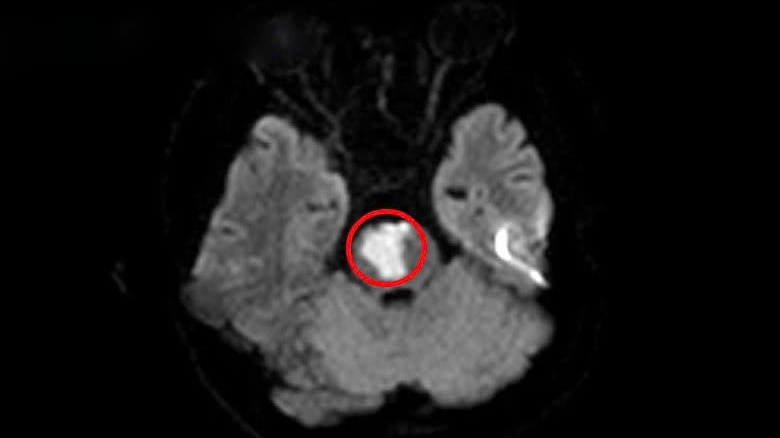

| Thanh niên 17 tuổi mắc kẹt trong đám cháy căn nhà 5 tầng trên phố Núi Trúc Chỉ trong 55 giây cặp đôi cuỗm gọn tài sản trị giá 200 triệu đồng Ngộ độc ma túy đá, nam thanh niên bị xuất huyết não |